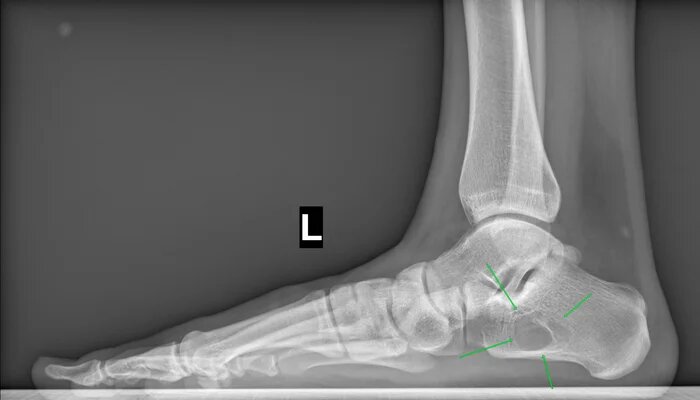

На Р-грамме левой стопы с нагрузкой: в структуре пяточной кости отмечается зона просветления костной ткани размером 29х27х17мм (точные размеры по данным КТ, которая была пройдена призывником),неправильной овоидной формы, с склеротическим контуром, соответствует кисте левой пяточной кости.

По заднему контуру таранной кости визуализируется добавочная кость- os trigonum размером 1.1х1.5см,наиболее вероятно вызывающая импиджмент-синдром заднего отдела голеностопного сустава.

Угол продольного свода левой стопы 160 град., высота 19 мм, соответствует продольному плоскостопию 3 ст. левой стопы.